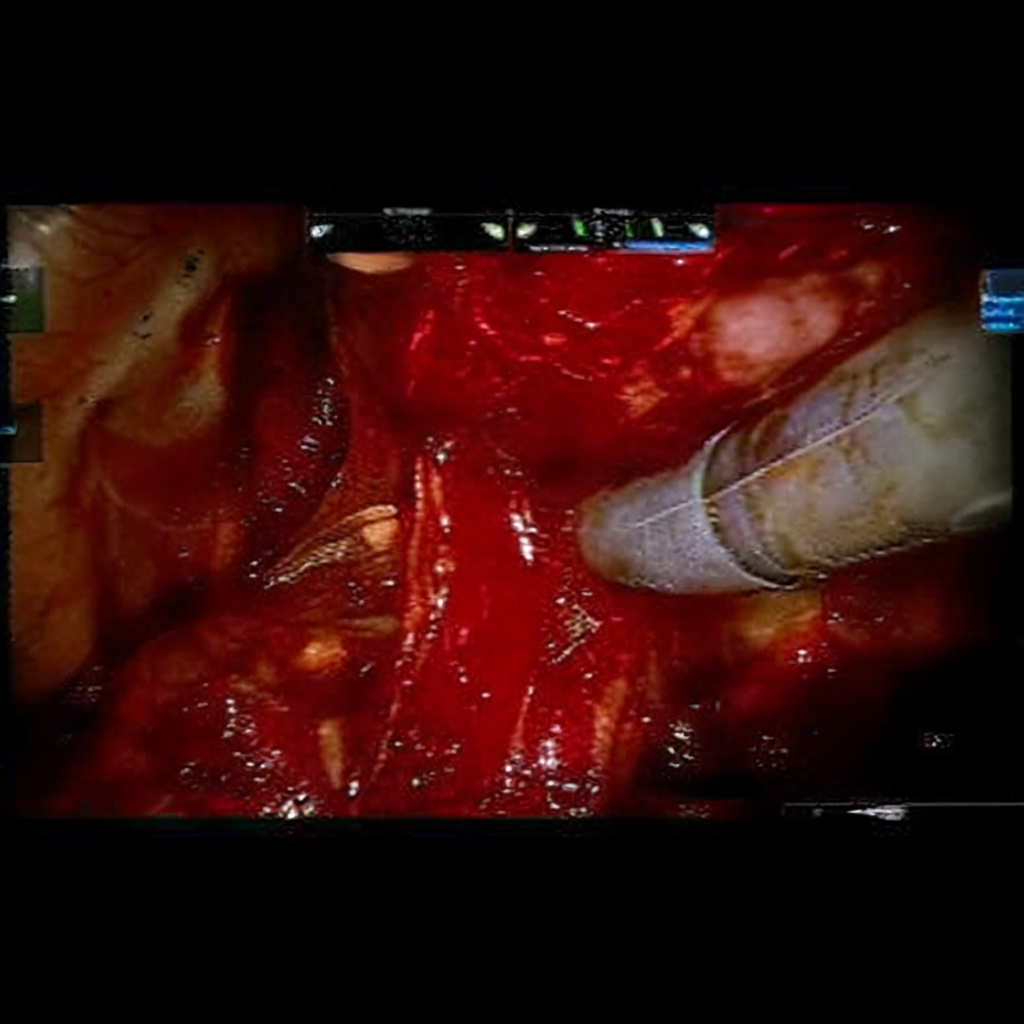

Diffusion models have recently gained significant traction due to their ability to generate high-fidelity and diverse images and videos conditioned on text prompts. In medicine, this application promises to address the critical challenge of data scarcity, a consequence of barriers in data sharing, stringent patient privacy regulations, and disparities in patient population and demographics. By generating realistic and varying medical 2D and 3D images, these models offer a rich, privacy-respecting resource for algorithmic training and research. To this end, we introduce MediSyn, a pair of instruction-tuned text-guided latent diffusion models with the ability to generate high-fidelity and diverse medical 2D and 3D images across specialties and modalities. Through established metrics, we show significant improvement in broad medical image and video synthesis guided by text prompts.

In this work, we focus on the ability of LDMs to generate novel datasets to overcome class imbalances traditionally associated with medical data, and potentially reduce the need for manual annotation of medical 2D and 3D data. We present MediSyn, a pair of text-guided latent diffusion models for broad medical 2D and 3D modality synthesis. To overcome the scarcity of labelled medical data, we leverage a vast corpus of more than 5 million image-caption pairs and 100,000 video-caption pairs collected from the public domain across numerous medical specialties, and integrate comprehensive natural language annotations to develop a pair of versatile diffusion models for the medical domain.

For Medisyn 3D, we compiled a total of 107,216 medical video-caption pairs, spanning 2 specialties and 3 imaging modalities. We performed model evaluation on a separate set of 200 pairs (100 from each specialty). Summary statistics for the entire dataset is provided in Table 1.

| General Surgery | 2,150,757 |

| Surgical Footage | 2,150,757 |

3.4 Video Generation

Video synthesis is notably more difficult than image synthesis primarily due to the need for both spatial and temporal coherence [37]. To help overcome this, we proceed with HiGen, a text-to-video LDM that decouples spatial and temporal processing across two distinct stages: structure and content [38]. HiGen incorporates a Variational Autoencoder (VAE) for encoding and decoding frames, a 3D U-Net for noise estimation (synthesis), and a frozen CLIP encoder for embedding textual prompts. In the structure phase, the U-Net incorporates the middle frames of the videos as spatial priors, alongside the corresponding embedded texts. To further increase temporal consistency, the content level introduces embeddings of motion and appearance variations from the corresponding videos. Motion vectors are derived from pixel-wise differences between consecutive frames, while appearance values are obtained from the image encoder of DINOv2 [39].

Similarly to Würstchen, we examined which components of HiGen required fine-tuning on our medical dataset, with the exception of the CLIP text encoder which remained frozen (Appendix Appendix ). Although the VAE was performant in encoding and decompressing our medical videos, the 3D U-Net failed to synthesize samples that resemble real medical data. Thus, we proceeded with fine-tuning the U-Net on our medical video-text pairs.

We loosely follow the original training method, incorporating several modifications. With equivalent compute (8 A100 80GB GPUs), we allocate half of the GPUs for video training and the other half for images: both spatial and temporal layers of the U-Net are not aligned to medical data. Prior to training, we preprocess the videos and compute their appearance changes using the ViT-B/8 version of DINOv2. For image training, we use the middle frames of the medical videos as the model inputs. We trained for a total of 10053 steps with a learning rate of 5e-5, covering roughly 3 epochs of the video dataset. We set the effective batch size for videos and images to 32 and 512, respectively. We dropped text captions 10% of the time. The entire training process was completed in roughly 12 hours.

Our findings demonstrate Medisyn’s remarkable ability to generate high-fidelity and diverse medical images, image sequences and volumetric scans across various medical subspecialties and imaging modalities. Other medical text-driven diffusion models, such as TauPETGen [42] for tau PET images and GenerateCT [43] for chest CT volumes, have proven successful in generating high-quality images that accurately depict anatomical features and clinical conditions. However, these models are constrained to a single imaging modality and anatomical region, thereby restricting their applicability. Moreover, they were trained on relatively small datasets sourced from a limited number of institutions, which could lead to more biased outputs. In contrast, Medisyn, having been trained on one of the largest publicly accessible medical image and video datasets to date, is equipped to synthesize data that cover numerous medical disciplines, population groups, and disease states. Leveraging our two models, we can synthesize new medical datasets as well as augment existing ones, potentially improving a wide array of medical machine learning tools, both general and specialized. Additionally, our models can minimize the need to repeatedly fine-tune on specific datasets for generating different imaging modalities, thus reducing computational costs for academic labs.

In summary, we introduced a pair of text-conditional LDMs trained on an extensive medical image and video dataset covering various medical subspecialties and imaging modalities. By generating high-fidelity and diverse medical 2D and 3D images, Medisyn illustrates the potential for a singular framework to broadly address the challenge of data scarcity in healthcare.